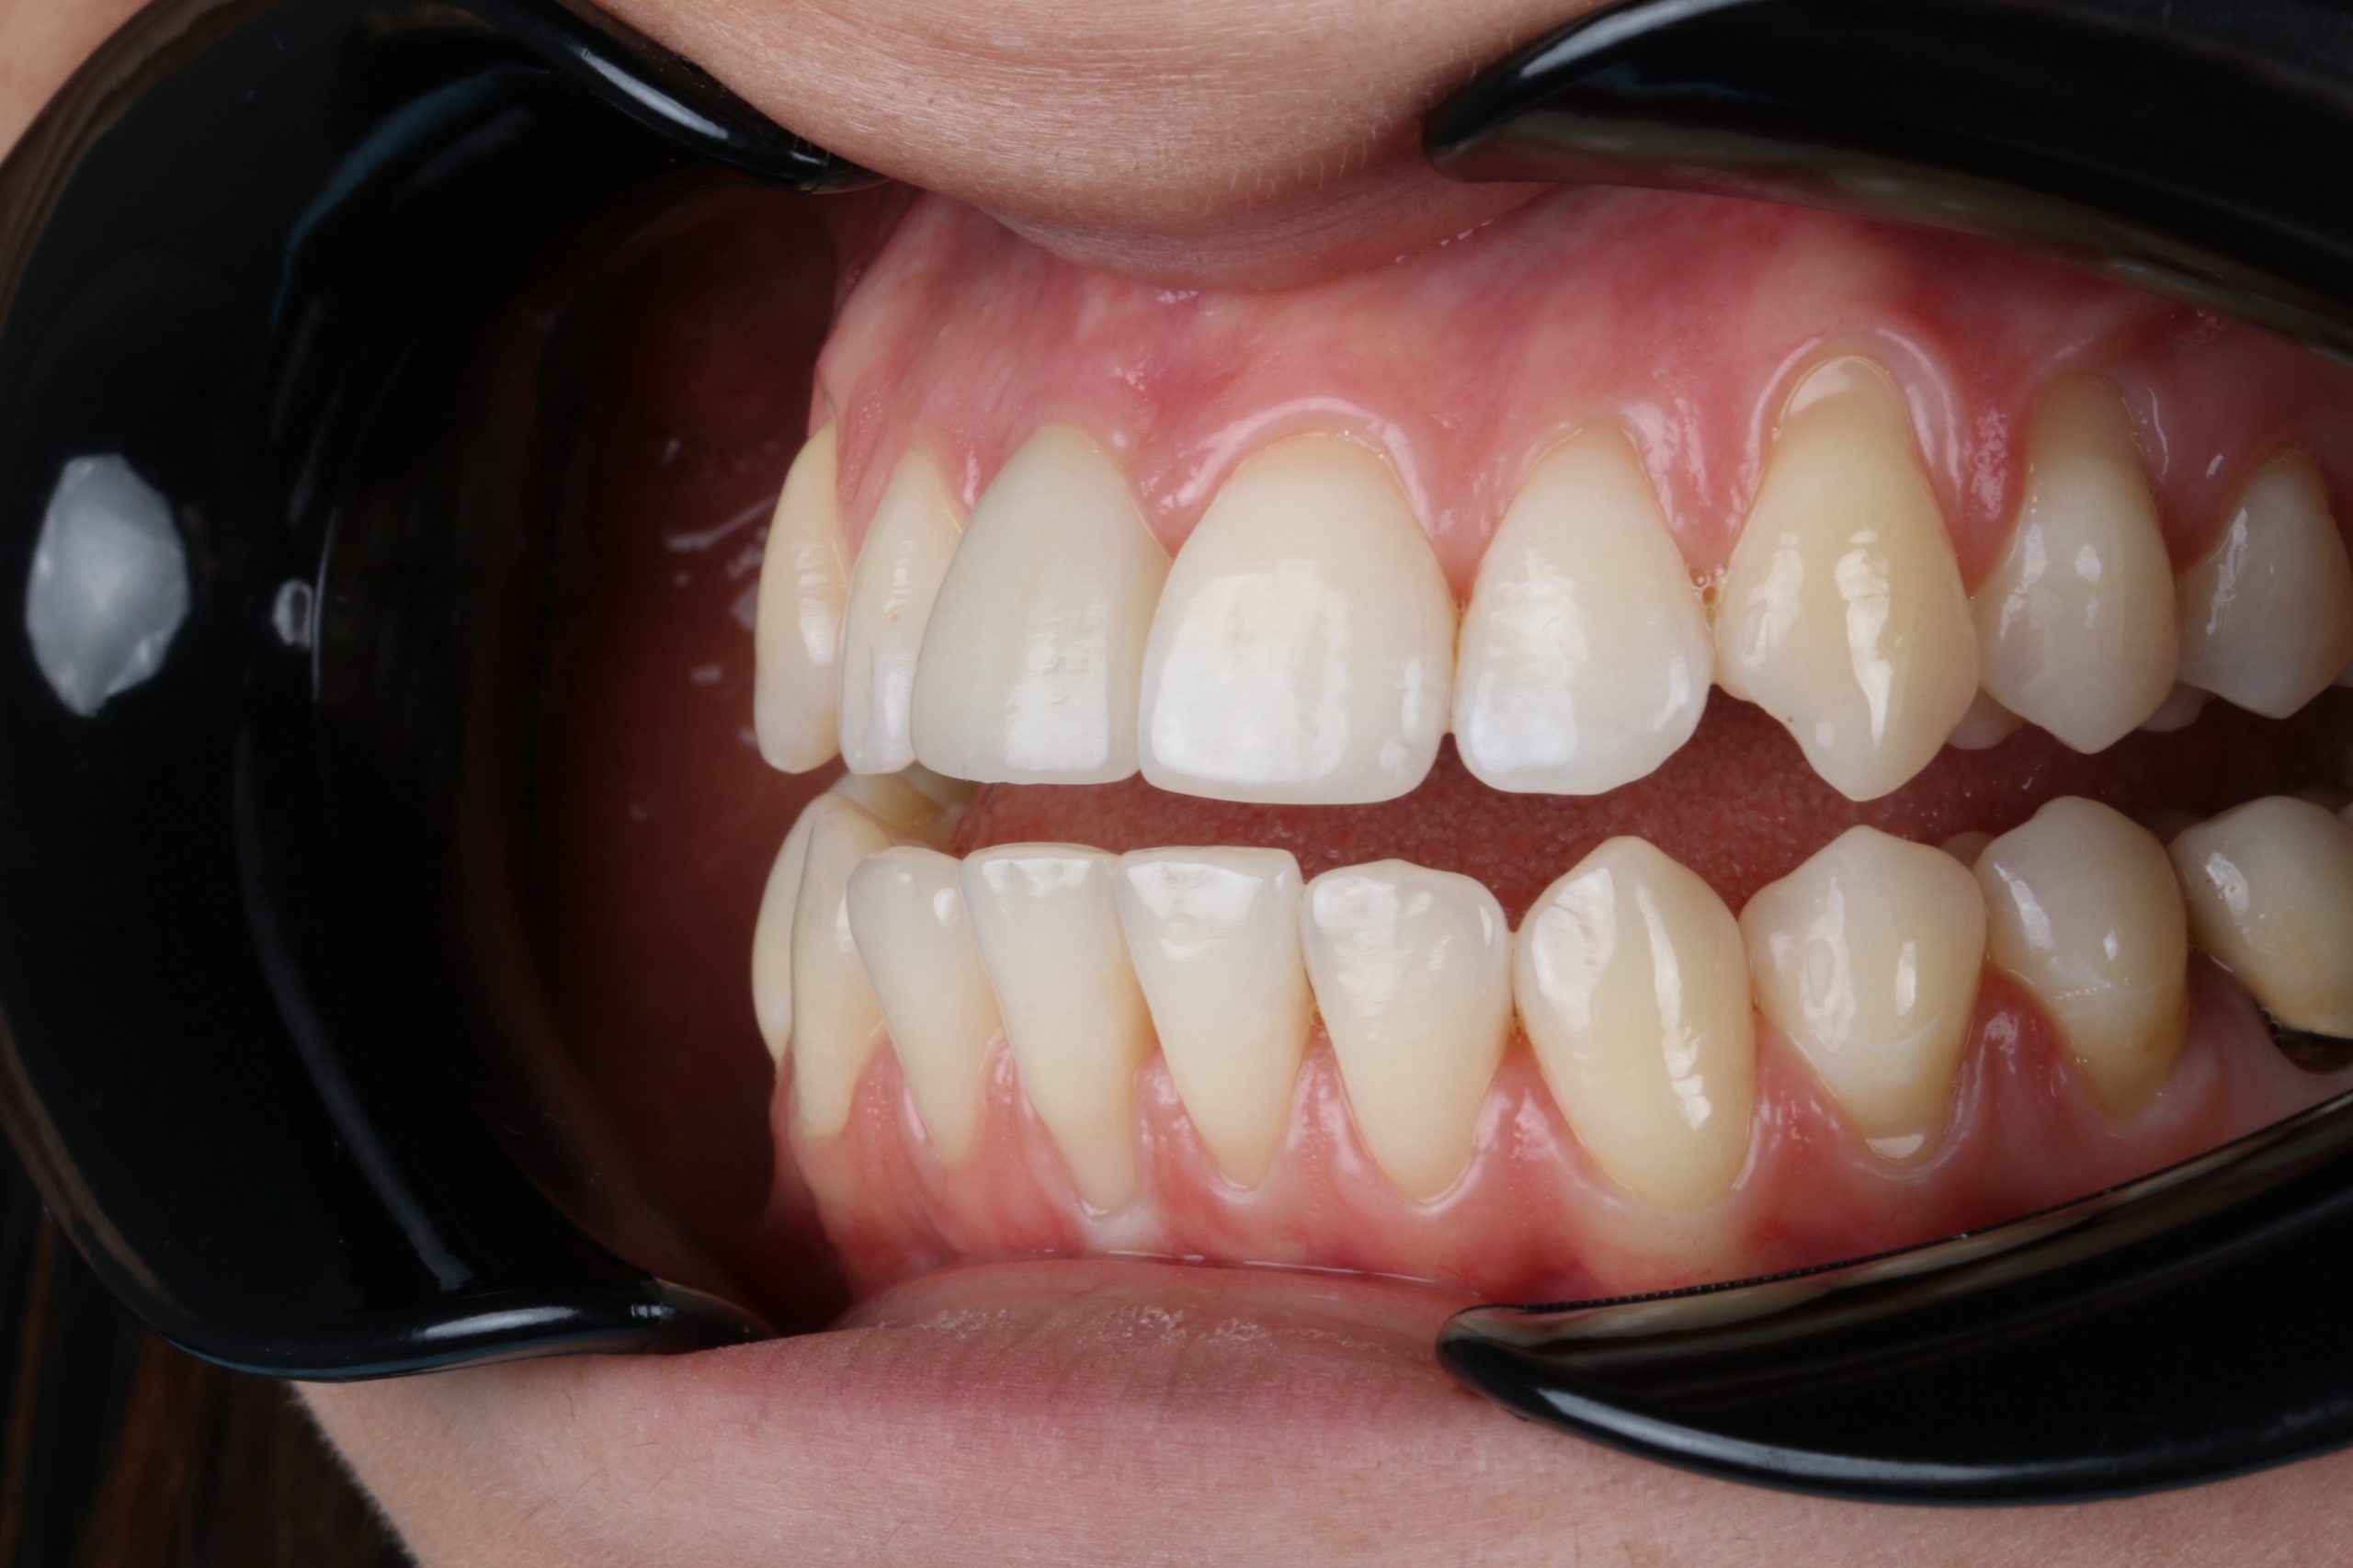

Коронки

От 33 500 Коронки фото